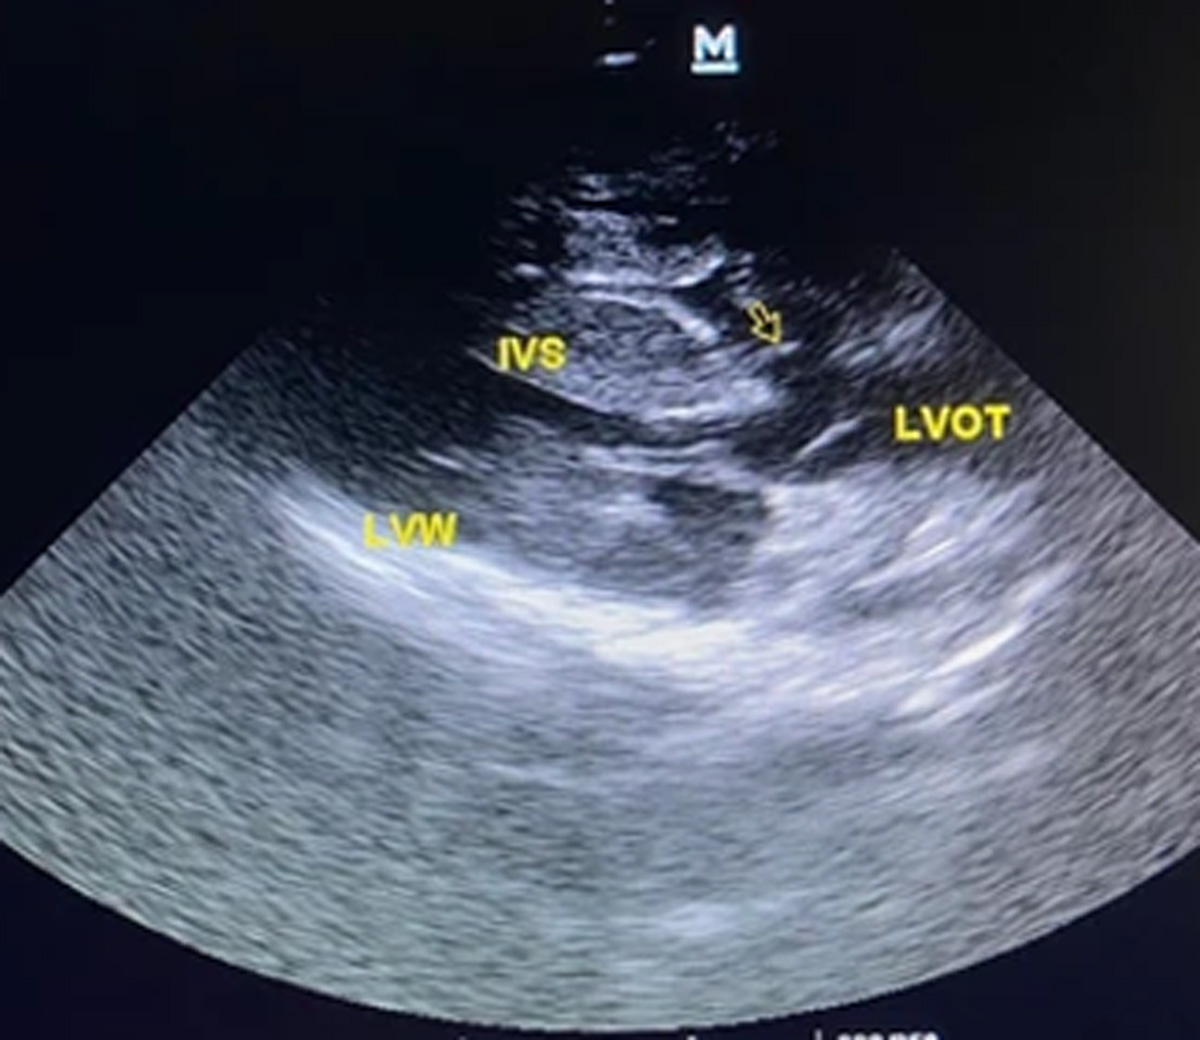

- Echocardiogram (Echo): An ultrasound of the heart that verifies the presence and size of the defect.